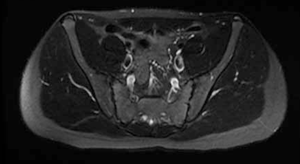

Se solicita hemograma sin alteraciones, velocidad de eritrosedimentación (VES) 28 mm/h y proteína C reactiva (PCR) 22,9 mg/l. Resonancia magnética (RM) de pelvis: proceso expansivo sólido en músculo psoas ilíaco izquierdo de 110 mm por 50 mm por 60 mm (Figura 1), RM columna lumbar: sin alteraciones. Frente al planteo de probable etiología tumoral, se solicita tomografía de tórax y abdomen normales, centellograma óseo: hipercaptación a nivel del proceso ya descrito.

Figura 1: Resonancia magnética, corte longitudinal (izquierda) y transversal (derecha) donde se visualiza hematoma de músculo psoas ilíaco izquierdo.